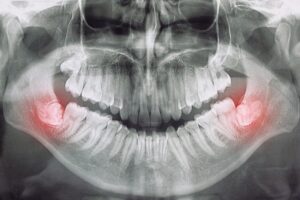

• Impacted wisdom teeth.

In most cases, wisdom teeth grow without problems, but occasionally they might not have enough room to come through properly. In this instance, they may grow at a difficult angle and cause what’s known as a tooth impaction.

This can cause a lot of discomfort, which is why you should always come and see us if your wisdom teeth are causing you trouble.

If left untreated, impacted wisdom teeth can lead to infection, so having the tooth removed will prevent any unpleasant symptoms and leave you with a happy, healthy smile.

It is a standard dental procedure to extract the third molars, often due to impaction, pain, or potential future problems. The procedure can range from simple extractions to more complex surgical removals, depending on the tooth’s position and eruption status.

• Impaction: Wisdom teeth can become impacted, meaning they are trapped under the gum or bone and cannot fully emerge. This can cause pain, infection, and damage to neighbouring teeth.

1. Assessment and planning: A dentist or oral surgeon will take X-rays /CBCT (3d scan) to assess the position and development of the wisdom teeth. They will determine the best course of action, whether it’s a simple extraction or a surgical removal.